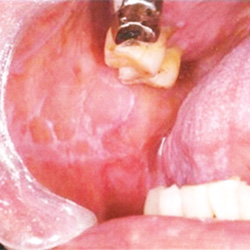

①金属アレルギーにより、前癌病変である「扁平苔癬」や「掌蹠膿疱症」を引き起こす可能性があります。

※扁平苔癬は、癌になる可能性がある粘膜疾患です。

数年経過した金属の詰め物の内側では、このようにすき間からむし歯が再発し進行するケースが多いです。